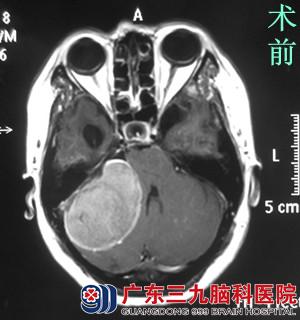

查体发现:潘女士神志清醒,右眼眼裂较左侧小,右眼睑下垂,睁眼乏力,右侧额面部触觉、痛觉、角膜反射明显减弱,右侧侧额纹、鼻唇沟变浅,嘴角向右偏斜,右侧皱眉、闭眼乏力,悬雍垂右偏,咽反射减弱。行头颅MR检查提示右侧桥小脑角区示一团块状占位病变,大小约6.29*4.29*2.37cm,相邻脑组织(脑干及右侧小脑半球)明显受压。

完善相关检查后,鲁明主任带领他的神经外科团队讨论。由于潘女士同时存在两个问题:脑肿瘤、面肌痉挛,考虑两个病变都在同一侧,最后一致决定一次手术解决两个问题。7月18日,由鲁明主任主刀,在全麻下行右侧CPA区巨大占位性病变切除术+右侧三叉神经微血管减压术。术中见肿瘤位于右侧桥小脑角区,黄白色,实性,质韧大小约5.5*5.8*4.9CM,术中电生理监测,予显微镜下电凝及超声刀分块切除,完整保留听神经、面神经、三叉神经、舌咽神经。术中见三叉神经周围蛛网膜粘连明显,予分离松解,见右侧小脑前下动脉分支明显压迫并包绕三叉神经,垫入Teflon棉,将血管与三叉神经隔离,并以生物胶固定,手术顺利结束。术后潘女士未见面部抽搐,术后症状均明显较术前好转。术后病理结果为:砂粒体型脑膜瘤(WHO I 级)。